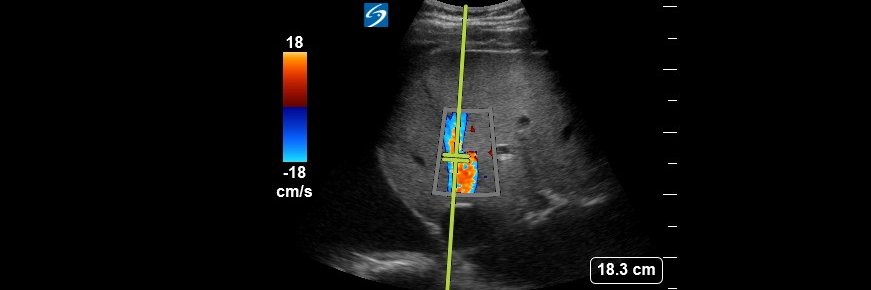

@MynephCC Great lesson. You have color/power Doppler by any chance? It’s difficult to differentiate between mass and clot unless you have recent imaging available.

@NephroP This pt with chronic retention had traumatic injury after multiple attempts for exchanging his catheter

Confirmation of Foley catheter placement is essential in patients with gross hematuria, especially prior CBI. While initial urine return may suggest correct placement, POCUS in this case demonstrated a persistently distended bladder with a large clot no Foley's in the bladder.